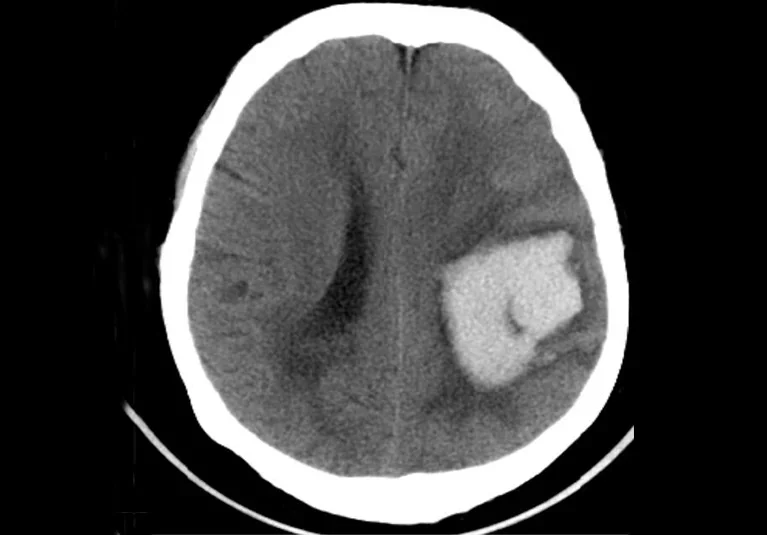

”Stroke care is evolving — and Mayo Clinic is helping lead the way.

From national clinical trials focused on improving hemorrhagic stroke outcomes to innovative recovery models that support patients and families, their multidisciplinary approach demonstrates a strong commitment to research, education, and patient-centered care.

Clinical trials like FASTEST, BLOCK-SAH, STRIVE-ON, and the family-focused C3FIT model are examples of how cutting-edge science is being translated into better care and hope for patients.”